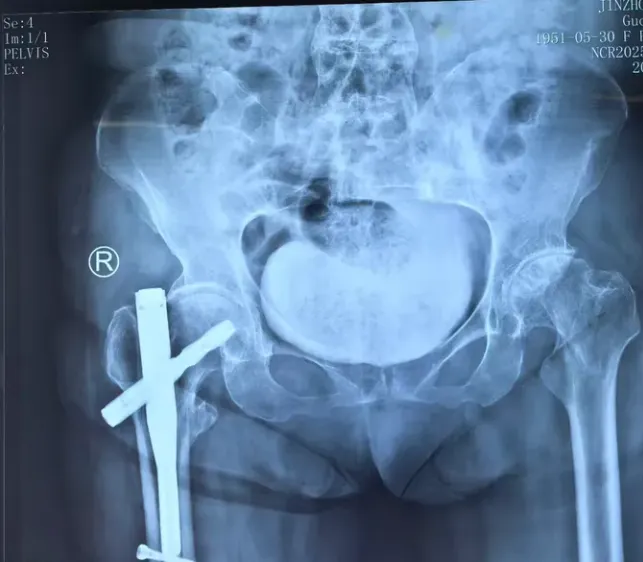

患者,女性,74岁,因先天性髋关节发育不良导致股骨头坏死多年,既往有多年的强脊炎病史,饱受腰痛及髋部疼痛煎熬,平素行走举步维艰,髋关节伸屈活动范围仅仅40º。本次因行走不便摔伤致股骨转子间骨折。

1. 强脊炎的关节置换手术难度非常大,因为术中髋关节黏连,活动度小,髋关节间隙不清,导致股骨头取出困难,而且术后髋关节因为脊柱的的竹节样改变,骨盆的倾斜角度容易脱位。

2. 强脊炎合并先髋的手术更是难上加难,因为先髋的患者髋臼浅且骨质差,假体包容差,容错率低,常常需要造盖来减少外展角,术中因骶髂关节骨性强直而致骨盆倾斜角度偏差,判断联合前倾角困难重重。

3. 股骨转子间骨折原则提倡复位固定,粗隆间骨折的患者做全髋关节置换手术难度徒升,此例患者因先髋,股骨头坏死多年,行全髋关节置换是唯一方案,更是三难合一难!因髋关节黏连,骨性强直,活动度差,术中钢丝捆绑骨折打入股骨柄也显得异常困难,而且极易导致骨折错位。